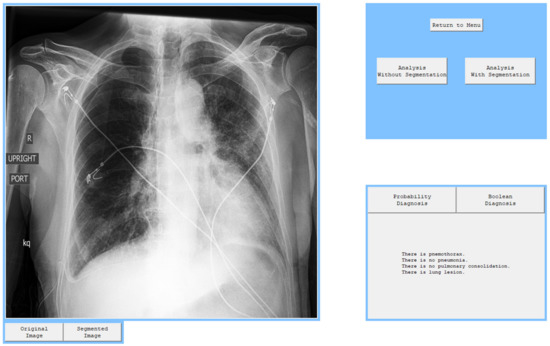

In order to present the operation of the models, a window application with basic functionalities was created in accordance with the MVC pattern architecture. It allows the user to load an image and analyze it with all four algorithms. It also performs an image segmentation and presents it on screen. All four diagnoses are performed separately in series and are independent, which means that the bad performance of one of them does not affect the performance of the other one.

After every model was tested separately, an attempt was made to check how all models combined into one program would diagnose all four pathologies. On the graphical user interface, it can be seen that there are two possible analyses, but as it was mentioned before, analysis with segmentation has considerably better results, so analysis without segmentation should be used when radiologists estimate that there is significant information outside the segmentation. There are also buttons that allow the user to switch between diagnoses presented in the form of probability and the boolean diagnosis. The application also provides buttons that can switch the view from segmented lungs to the original image.

The program works smoothly and diagnoses pathologies correctly on the testing set. Sample diagnoses were presented in Figure 8, Figure 9 and Figure 10. The radiologist can use this application to analyze one or many images very quickly and obtain one specific diagnosis. If they accept this diagnosis, they can go on and check the next patient and if they have doubts, they should check their diagnosis again and maybe change their verdict. As it is presented, the segmentation process also works without problems and shows the image that can help the radiologist to focus attention on what is essential and not become distracted with worthless information.

Figure 8. Diagnosis of patient with pneumonia.